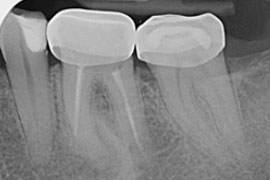

Aktuelle Röntgenbilder sowie eine symptombezogene Untersuchung des zu behandelnden Zahnes sind Grundlage für unsere Beratung über Prognosen der Therapie, Behandlungsalternativen sowie Behandlungskosten.

Die Wurzelfüllung

Die Wurzelfüllung dient dem bakterien- und flüssigkeitsdichten Verschluss des Wurzelkanalsystems und ist neben der Desinfektion wichtiger Bestandteil der 2. Behandlungssitzung.

In den meisten Fällen wird der Zahn mit Guttapercha (ein kautschukähnliches Material) gefüllt. Durch Erwärmung lässt sich dieses Wurzelfüllungsmaterial fließfähig und sicher in alle Bereiche des aufbereiteten Kanalsystems applizieren. Als letzter Schritt wird der Zugang in der Zahnkrone mit einer bakteriendichten und stabilen Füllung verschlossen. So vorbereitet kann der Zahn wieder aufgebaut oder im Regelfall mit einer Krone versorgt werden.